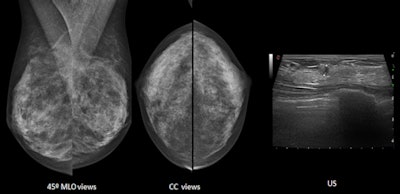

Both mammographic views (mediolateral oblique and craniocaudal) are normal on these heterogeneously dense breasts. Ultrasound detects a 5-mm invasive ductal carcinoma. Images courtesy of Dr. Luis Pina Insausti.Handheld ultrasound can only be performed for selected patients in a clinical setting, and it cannot be offered in a screening setting for all patients, he explained. Automated breast ultrasound, on the other hand, can play a central role in increasing the detection of additional cancers in the screening of dense breasts; the technologist performs the examination and later the radiologist reads the images.